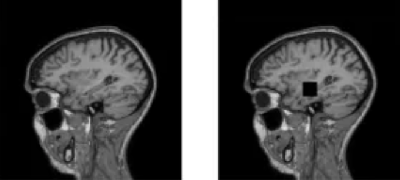

Разработка, генерирующая и анализирующая синтетические МРТ-снимки головного мозга, предназначена для специалистов медицинских информационных технологий, кроме того, платформа позволяет обучать нейросетевые модели.